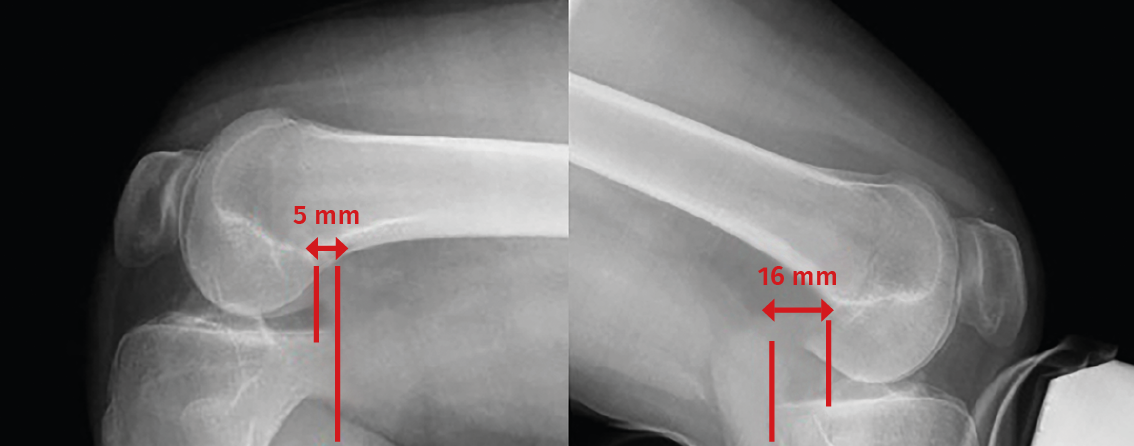

• Posterior drawer test. This is done with the patient in supine decubitus and the knee in 90° flexion. The test involves the application of pressure in a posterior direction of the proximal region of the tibia, observing posterior tibial translation in the injured knee with respect to the contralateral knee (Figure 2). A posterior displacement of the tibia of 0-5 mm is considered to correspond to a grade I lesion, 6-10 mm to a grade II lesion and >10 mm to a grade III lesion. Assessment of the degree of displacement is subjective, and thus implies important interobserver variability. If the tibial plateau remains located anterior to the medial femoral condyle, the lesion is considered to correspond to grade I, while if it is located at the same level as the femoral condyle the lesion corresponds to grade II, and if the plateau extends beyond the medial femoral condyle, the lesion corresponds to grade III (Figure 2)(10,11).

Figure 2. Initial position of the tibia reduced in the posterior drawer manoeuvre (A) compared with posterior tibial translation without reduction (B).

The classification of PCL injuries according to the observed posterior translation is as follows:

– Partial injury of the PCL if there is an increase in posterior translation of <8 mm.

– Isolated complete injury if translation is between 8-12 mm.

– Injury of the PCL with other associated lesions (posterolateral or posteromedial) if there is >12 mm of posterior translation.

Posterior translation of the tibia is measured as the minimum distance between a line tangential to the posterior cortical layer of the tibia and another line tangential to the posterior margin of the femoral condyle at the most dorsal point of the Blumensaat line (Figure 5)(12,13).

Figure 5. Telos system. The red line indicates measurement of posterior translation of the tibia: the difference between the healthy right knee and the left knee is 11 mm in this case - suggestive of isolated complete posterior cruciate ligament (PCL) rupture.